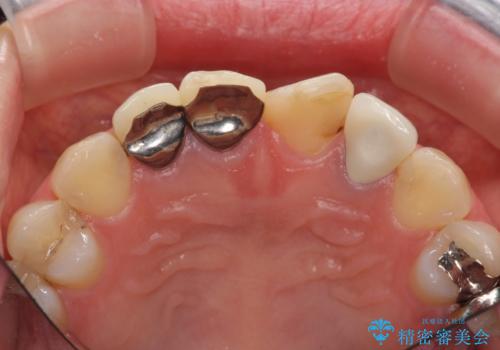

- 前歯を天然の歯のようにきれいにやりかえたいと希望され来院されました。

根尖病変の存在が判明したため、感染根管治療後にオールセラミックジルコニアクラウンを製作します。

- 37万円(仮歯×3・ファイバーコア×2・ジルコニアクラウン×3)費用は治療当時の料金となります